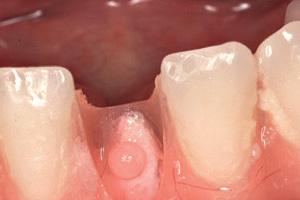

RL8: IAC was seen running between the buccal root which was hooked mesially and lingual roots at its apex, vulnerable to surgical injury (Fig 3).

On discussion with the patient, keeping in mind the clinical and CBCT findings, the option of coronectomy was suggested for LL8 and RL8. If roots become loose during the procedure, then complete removal. The patient consented to have her wisdom teeth removed and coronectomies for the lower wisdom teeth under general anaesthesia.

A standard coronectomy technique for removal of RL8 tooth was carried out. Lingual periosteum was not reflected to avoid lingual nerve injury. Following sectioning and trimming of the tooth until the cementoenamel junction (CEJ), there was insufficient soft tissue to achieve primary closure of the socket.

To achieve good primary closure, it was decided to modify the procedure and trim the roots up to the furcation to ensure a sound collar of alveolar bone and advance the buccal flap. This modification helped significantly during primary closure of the socket. LL8 tooth was removed completely as the roots became loose as well as UR8 and LU8. The post-operative phase was uneventful, and she recovered well (Fig 4).